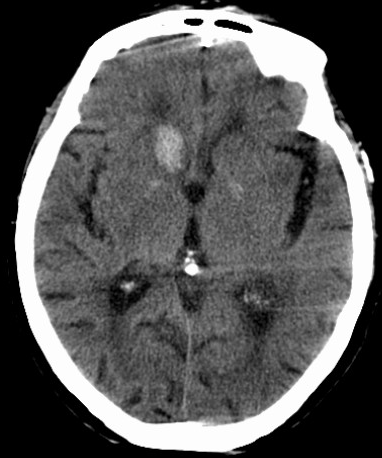

脑出血最常见的部位是基底核区脑出血,包括壳核出血和尾状核头出血。

壳核出血

影像学表现分为三型:

责任血管:豆纹动脉,尤其是豆纹动脉外侧支

病因:高血压动脉硬化